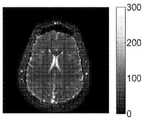

도 13은, 에코 분할을 사용하여 MRF로부터 생성되는 T1, T2, 및 M0(순(net) 자기화) 맵들을 도시한다.

Figure 13 shows the T1, T2, and M0 (net magnetization) maps generated from the MRF using echo partitioning.

도 13은, QUEST MRF로부터 동시에 생성된 T1 맵(1400), T2 맵(1410), 및 M0 맵(1420)을 도시한다. 이들 맵들은 에코 분할 접근법을 이용한 가능한 결과들을 도시한다.FIG. 13 shows a